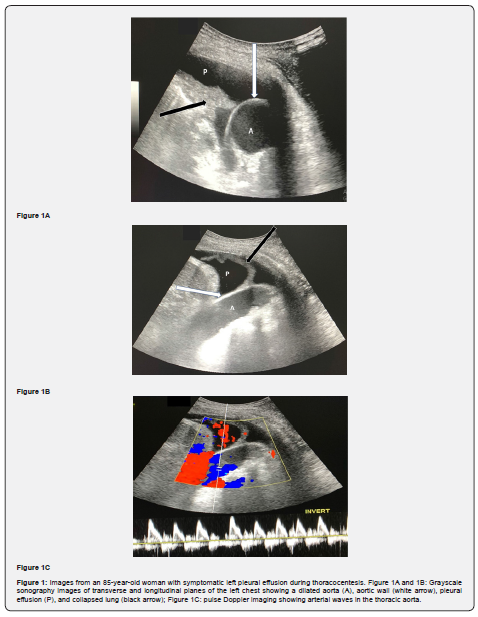

Left thoracentesis was planned with intention to disrupt the mentioned pleural septation for proper drainage. During the ultrasound guided thoracentesis, the echogenic linear structure was the wall of dilated aorta reaching the posterior chest wall. The diagnosis was made after using grayscale sonography transverse and longitudinal planes and pulse Doppler sonography. After that ultrasound guidance left thoracentesis performed safely without complications (Figure 1).

Ultrasound is a useful imaging modality for the evaluation of pleural pathologies such as effusion. It can also be used to visualize the intercostal artery by Doppler during thoracenteses for the prevention of vascular injury [9]. The thoracic aorta, however, cannot usually be visualized via percutaneous ultrasound due to the overlying air-filled lung. In elderly patients, the aorta can also be dilated and even opposed to the posterior chest wall. Both a dilated aortic lumen and pleural effusion demonstrate fluid echogenicity, and, in such cases, the aortic wall can sometimes be mistakenly identified as a collapsed lung or a pleural effusion septation. Sonography using multiple techniques, including color and pulse Doppler, as well as using several imaging planes, can facilitate better visualization and delineation of the thoracic aorta from pleural effusion or a collapsed lung [10].